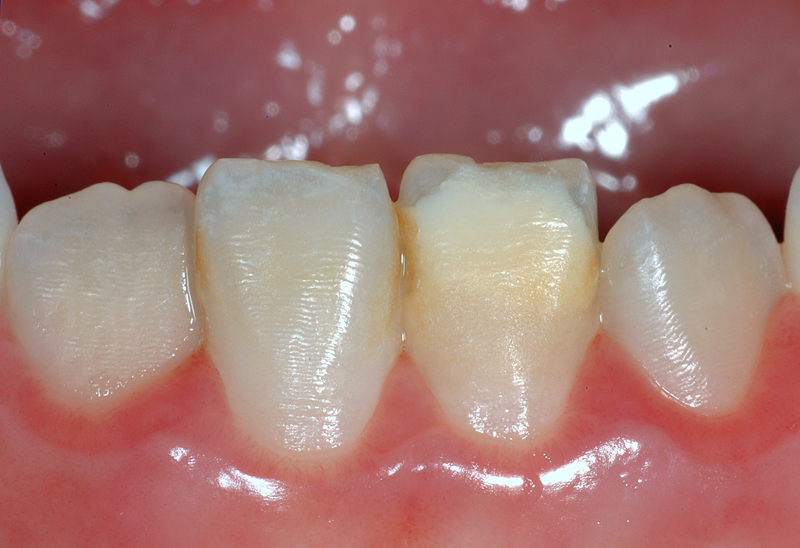

Hier ein weiterer Fall mit weissen / gelblichen Flecken an einem unteren linken mittleren Schneidezahn (Zahn 31). Diese Flecken gehen gegen den Zahnfleischrand ins Gelbliche über. Die grossflächigen Flecken auf der Zahnaussenseite sind durch eine Zahnschmelzbildungs-Variation bedingt und «im Zahn drin».

Zudem hat der Zahn 31, wie die anderen auch, braune Auflagerungen im Bereich der Zahnzwischenräume. Diese Verfärbungen lassen sich in der Regel gut reinigen und entfernen.

Ebenfalls gut sichtbar auch hier die Perikymatien (die Querrillen).

- Weisser / gelblicher Fleck an einem 31